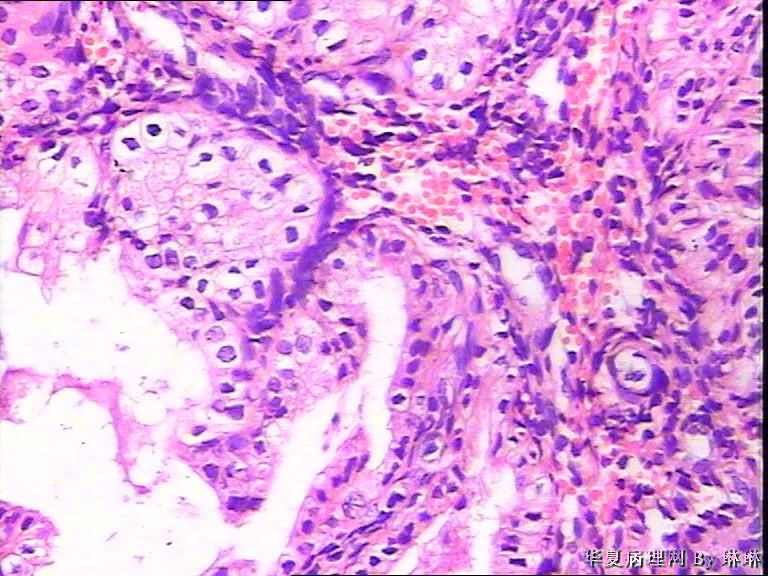

患者女性,38岁,月经量多4个月,曾服用止血药物,无其他病史。

• 子宫内膜,请教图2

图2

腺体呈高度分泌反应,我们必须结合病史,考虑是否药源性反应,或持续黄体期子宫内膜.

晚泌期宫内膜,并见A-S现象

开始临床没有提供怀孕的病史,后来我们有咨询临床科室,大夫还是说没有用药、月经正常,刚过了经期,月经量多,这次月经持续时间长入院。所以我们开始排除了高度分泌的A-S反应,看到腺体增生呈乳头状,还有异型性,而且镜下部分子宫内膜还有增生期改变的,不完全是高度分泌的。再三考虑后还是要求临床查了血HCG,结果显示HCG370多。最后我们发了单纯性增生伴高度分泌。